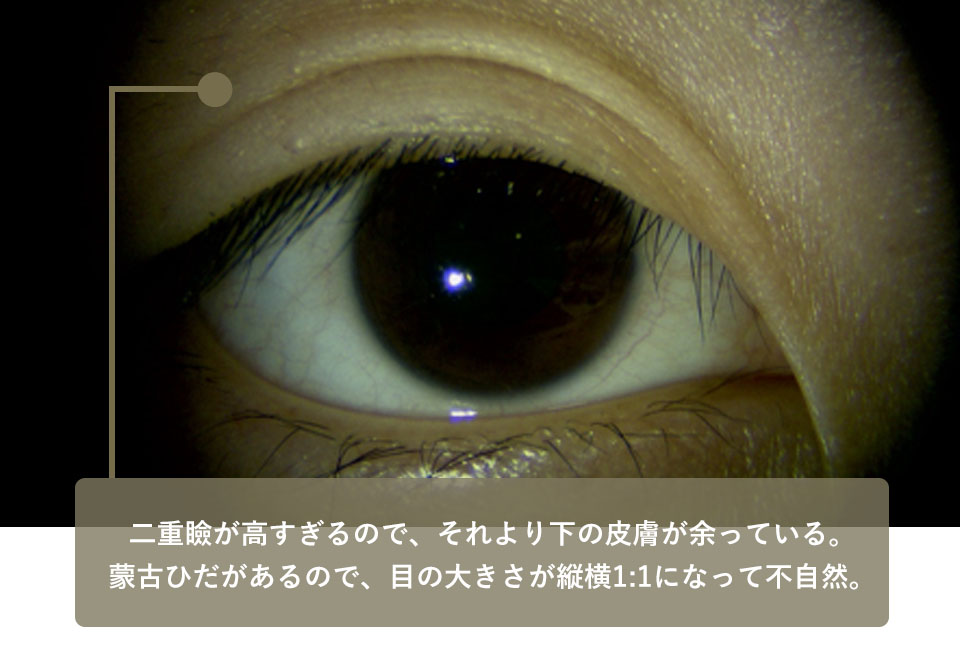

The patient came to our hospital for revision of an implantation surgery she had undergone a year ago at a major D cosmetic surgery center because the shape of her eyelids had become unnatural after the surgery. As in case 2, this patient also has sagging skin below the eyelid because the eyelid is positioned too high.

There is another problem. This is the protrusion of the skin at the inner corner of the eye, which is also known as the mongolian folds. This is also known as the Mongolian folds, and is more common among Asians, especially East Asians.

Because the Mongolian folds are stretched, no matter how beautifully the upper eyelid is made, it will be pulled downwards and will not result in a beautiful double eyelid line.

| Before surgery | The double eyelid is too high and there is a mongolian fold with excess skin below it, making the eye size 1:1 in length and width, which is unnatural. |